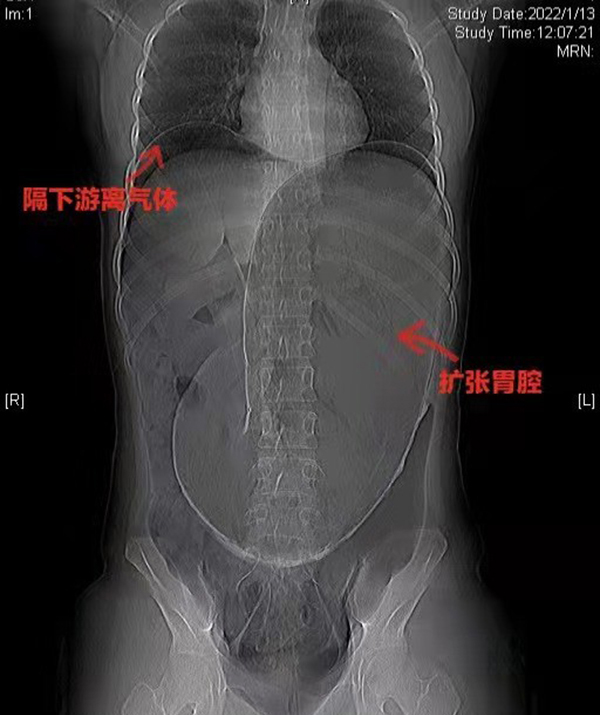

黃淮網(wǎng) 20222年1月13日,伴隨著急促的救護(hù)車鳴笛聲,徐州醫(yī)科大學(xué)附屬醫(yī)院急診中心接診了一位特殊的患者。一位年輕的女性,肚脹如鼓,腹痛難忍。急診外科迅速完善初步檢查并聯(lián)系胃腸外科會診。此刻,時間就是花季少女的生命!胃腸外科張秀忠主任團(tuán)隊(duì)立刻投入到緊張有序的治療中。經(jīng)過問診、查體、影像學(xué)檢查等綜合診斷后判定患者胃腔極度擴(kuò)張、膈下游離氣體,提示消化道穿孔。此時患者已有休克表現(xiàn),病情危急,隨時有生命危險,需急診手術(shù)處理。